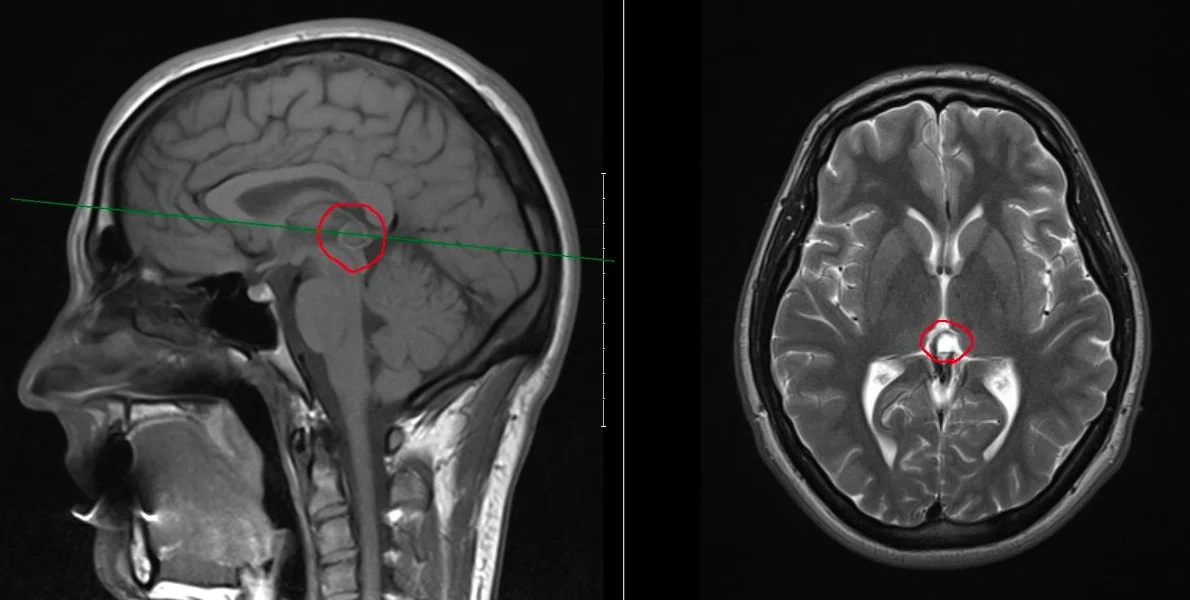

Evan's severe, debilitating neurological symptoms from the cyst in the middle of his brain include severe and chronic migraines, dizziness, memory loss and vision problems. These have prevented him from being able to continue his studies or have any kind of life.

The pineal cyst in Evan's brain